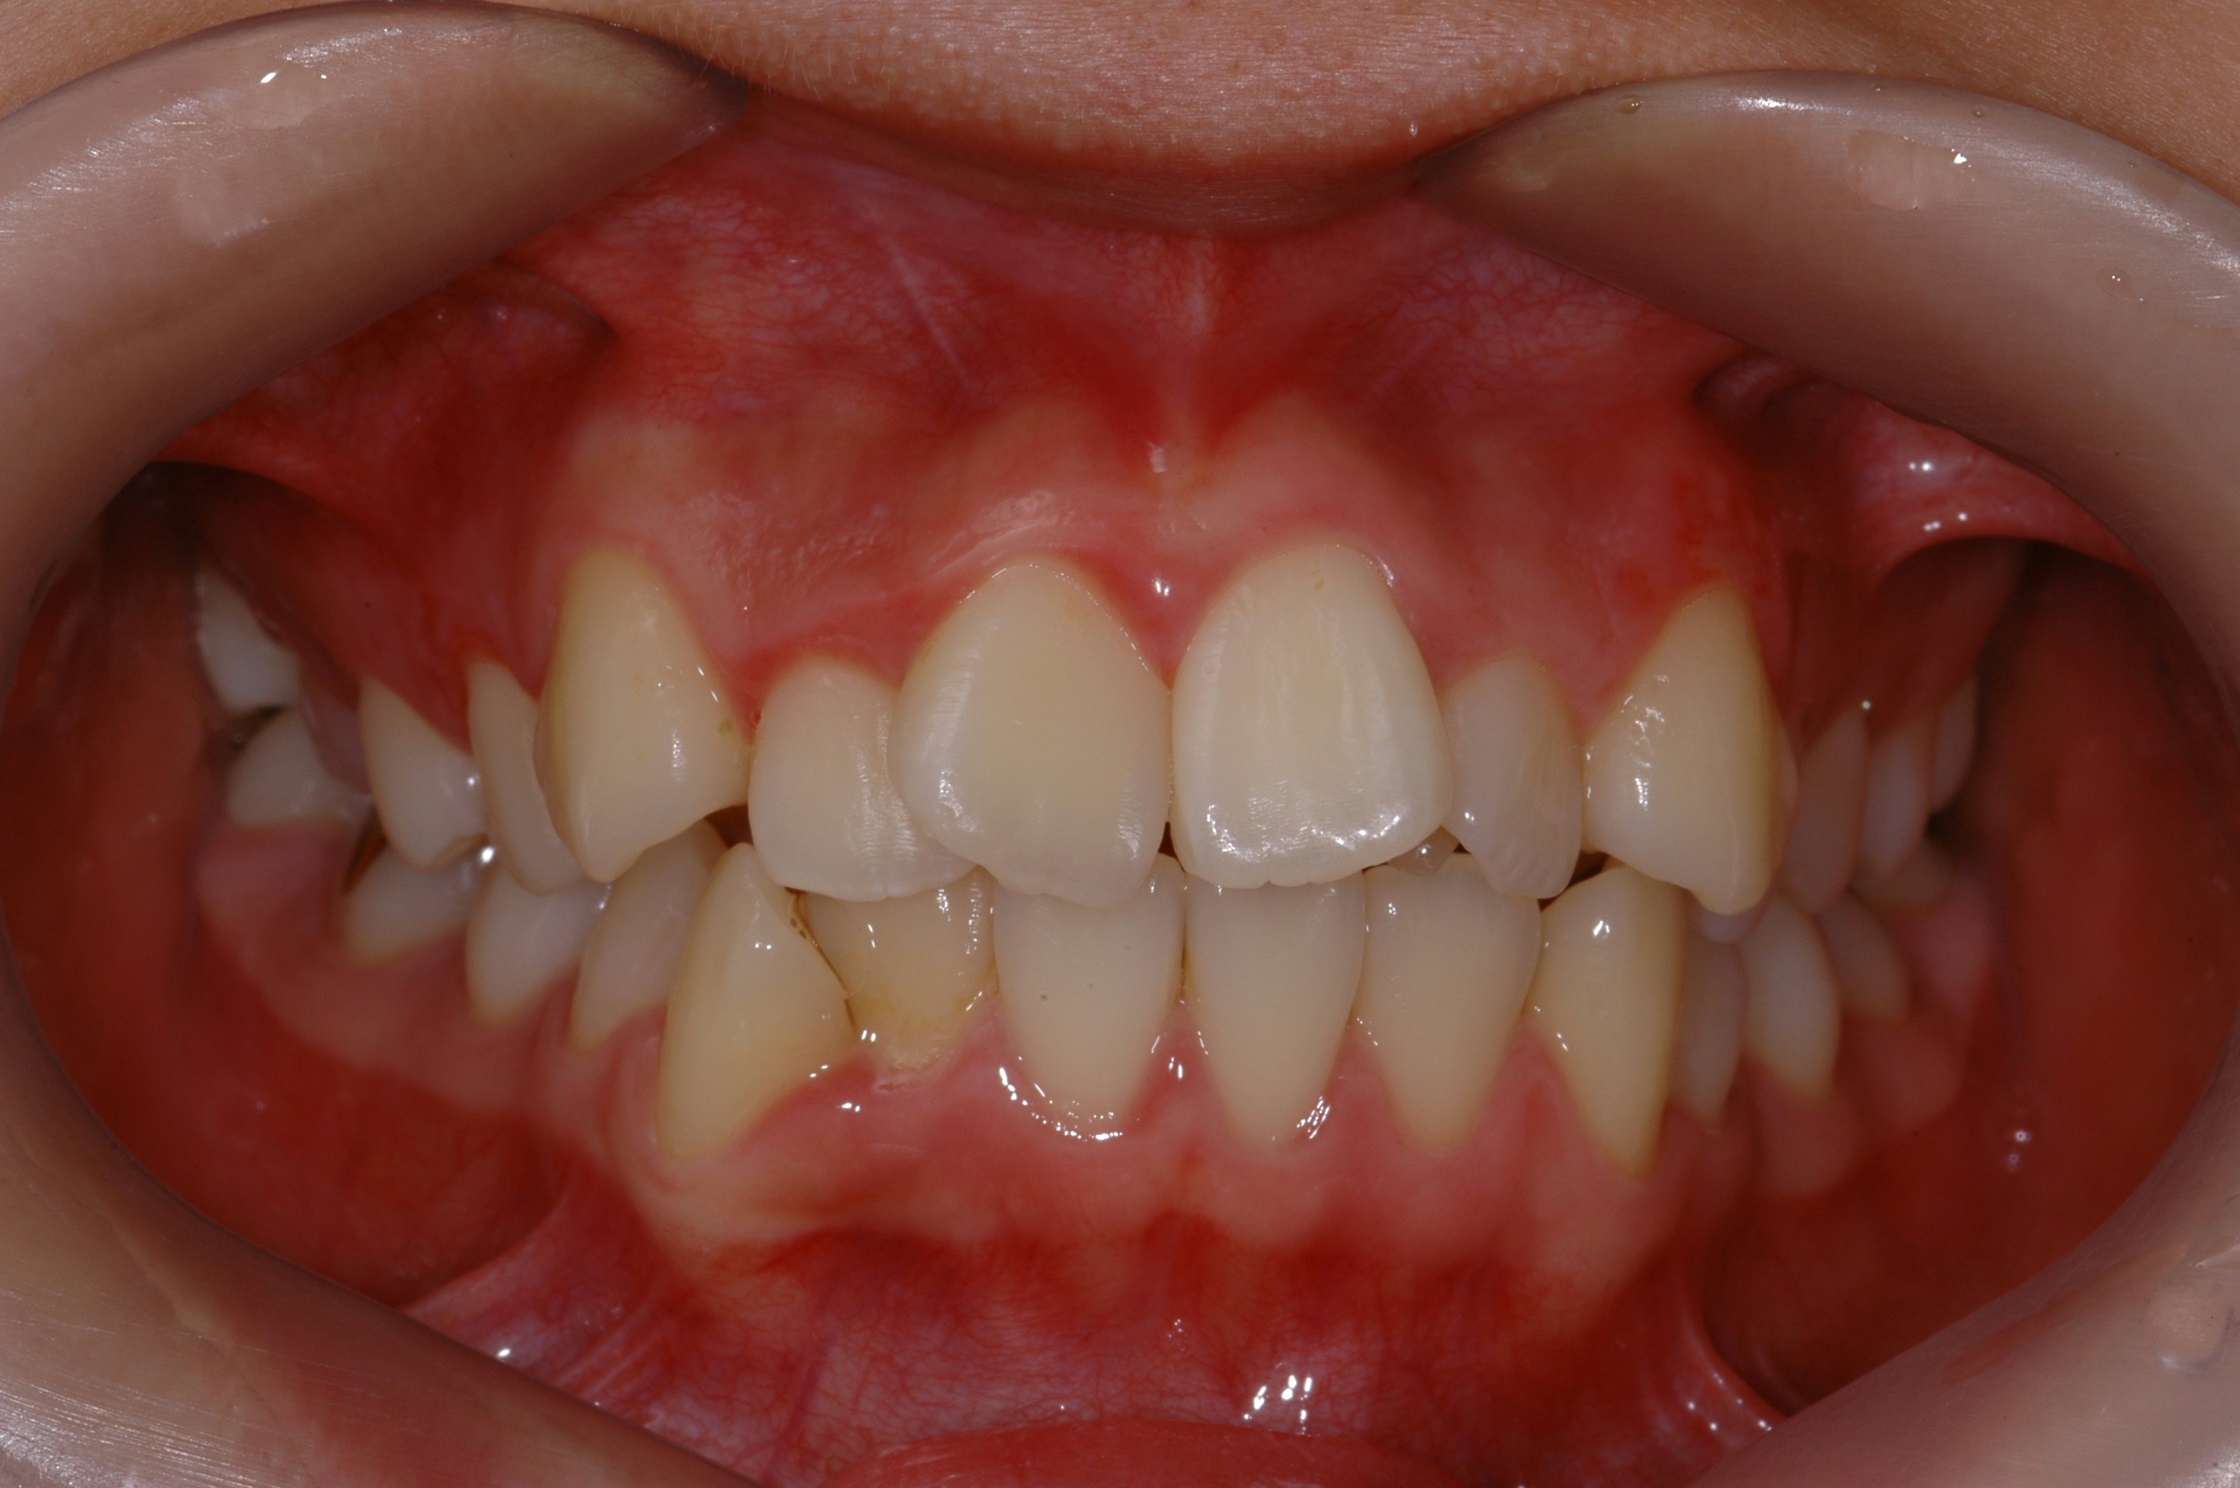

치료 전 사진입니다.